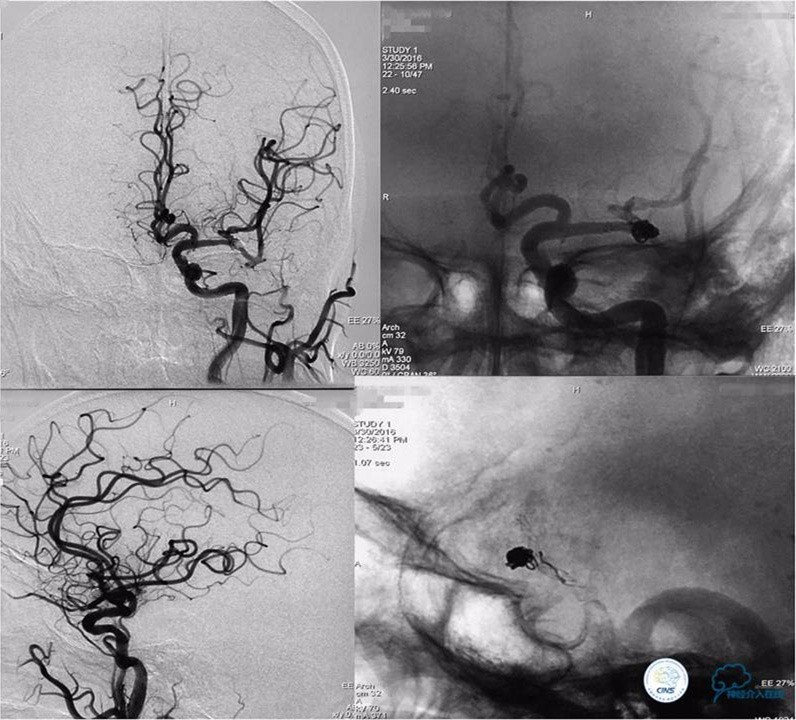

入院后DSA检查:

造影显示:基底动脉重度狭窄,狭窄率90%;基底动脉动脉瘤,大小6.71mm×3.55mm,瘤颈宽为4.51mm。

手术经过如下:

路径图下沿导引导管送入TRANSEND微导丝(0.014″长度300cm)小心通过狭窄段至左侧大脑后动脉P3段,沿微导丝送入Gateway球囊(2mm×22mm)至狭窄段,准确定位后球囊逐渐加压至7atm,可见球囊完全张开,快速抽瘪球囊,造影显示狭窄段较前明显改善,残余狭窄率约70%,考虑到球囊扩张后仍有较高残余狭窄,为防止弹性回缩导致再狭窄及血栓形成,尽快行支架置入术。

撤出球囊,沿微导丝送入ENTERPTISE (4.5mm×22mm)自膨式支架至狭窄段,准确对位后成功释放支架,造影显示双椎动脉颅内段及基底动脉前向血流好,支架贴壁良好,动脉夹层消失,残余狭窄约30%。支架释放完成后,微导管经支架网眼导入瘤腔内,送入弹簧圈数枚并解脱。手术结果如下:

术后工作位造影

术后右斜位和左斜位造影显示动脉瘤完全栓塞